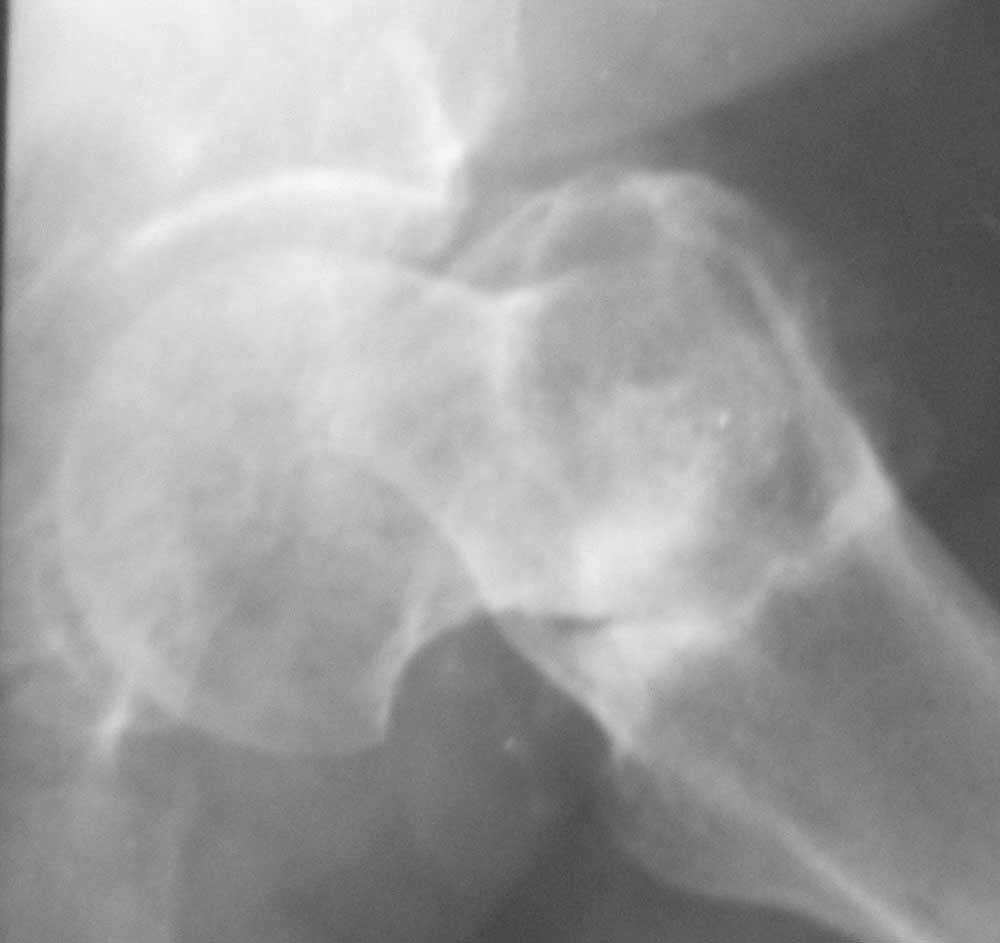

Больная 61 год. Травма 1 год назад – закрытый базальный перелом бедренной кости без смещения. Перелом рентгенологически был диагностирован только через 6 недель (на первичных снимках не визуализировался, КТ не проводилось, повторную травму отрицает). Проведен курс консервативного лечения (ходьба на костылях без опоры на левую ногу до 4-х месяцев, ЛФК, физиолечение и т.п.).В настоящее время передвигается при помощи костылей с незначительной опорой на левую ногу. Больная страдает сахарным диабетом.Возможные варианты лечения: 1) Тотальное эндопротезирование.2) Ревизия ложного сустава, возможно костная пластика, МОС углообразной пластиной 130, DHS, AFN.

Здесь сустав интактный, так что эндопротезирование избыточно. Нужна коррекция шеечно-диафизарного угла и ротации, и затем фиксация. Если вправить получается за счет подвижности несращения - то закрыто синтезировать, как свежий перелом любым доступным подходящим имплантатом. Если не вправляется - дополнить вальгизирующей остеотомией.

Для дообследования надо сделать снимки в максимальном приведении и отведении. Снимок с отведением можно будет сделать уже в условиях анестезиии, когда можно ожидать и большего.